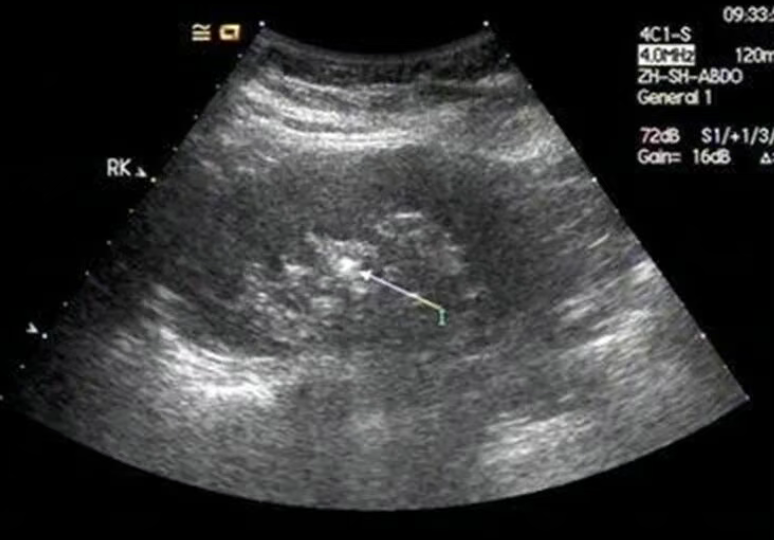

B超是肾结石筛查的首选,便捷无创且能发现大部分结石,但它并非万能。通俗来讲,超声查结石就像夜晚找星星,大的、回声强的易识别,小的、回声弱或位置隐蔽的则容易漏检。

不同成分结石(如草酸钙、磷酸钙结石等),超声下回声强度不同,部分质地疏松、回声弱的结石,体积较小时更难被发现。

大小因素4mm以下微小结石,超声分辨率有限,检出概率低,小张的7mm结石大概率是由小结石逐渐增大形成。

结石“年龄”区别新形成的结石质地软、回声弱,不易识别;随时间钙化、质地变密后,回声增强,更易被B超捕捉。